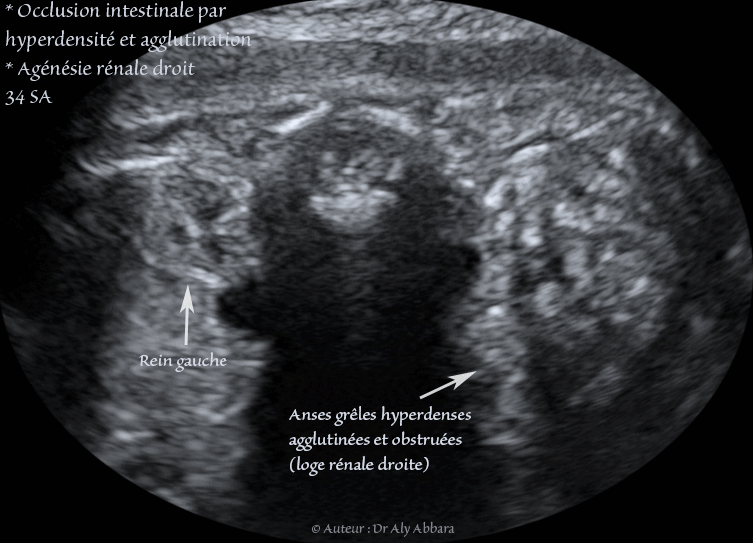

Images échographiques montrant une occlusion intestinale se manifestant par la dilatation des anses grêles et un hyperpéristaltisme.

Cette occlusion intestinale est liée à la présence, dans la fosse iliaque droite, comme on le voit sur ces images, d'un magma d'anses grêles hyperdenses, agglutinées et obstruées.

* Une agénésie rénale unilatérale droite